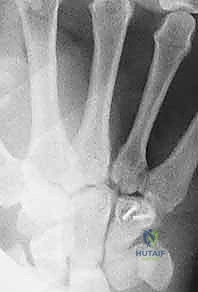

- الأشعة السينية بوضعيات خاصة: أخذ صور بأكثر من زاوية لفك تراكب العظام.

- الأشعة المقطعية (CT Scan): المعيار الذهبي لتشخيص كسور عظام الرسغ المخفية وتحديد حجم التفتت والتزحزح.

شاب رياضي (25 عاماً) سقط أثناء ممارسة كرة السلة وعانى من ألم مزمن في قاعدة اليد لمدة 3 أشهر، تم تشخيصه خطأً على أنه التواء. بعد زيارته لعيادة الدكتور هطيف، أظهرت الأشعة المقطعية الدقيقة كسراً في "خطاف العظم الكلابي" (Hamate hook fracture). تم إجراء عملية جراحية دقيقة لاستئصال الجزء المكسور الصغير الذي كان يضغط على الأوتار. بعد 6 أسابيع من التأهيل، عاد اللاعب لممارسة الرياضة بكامل كفاءته.